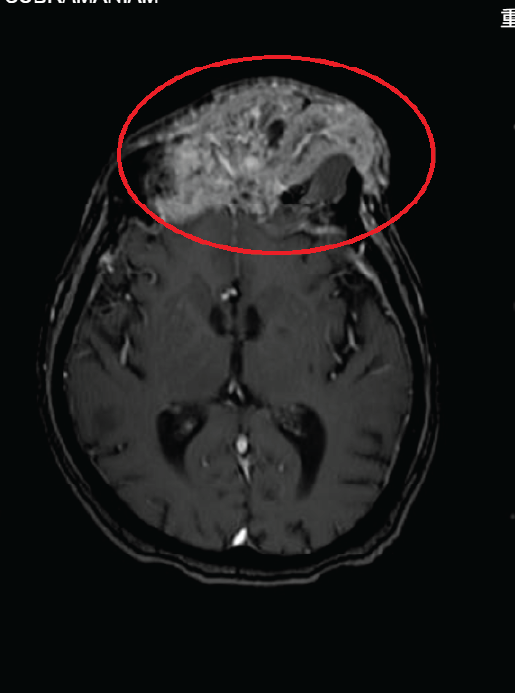

Clinical Considerations: Advanced age and frailty; surgery not recommended due to high risk of vision loss. Non-invasive treatment prioritized.

• Treatment Area: Forehead and left ocular region

• Expected Outcome: After 10 sessions, significant reduction in forehead tumor size with gradual repositioning of the eyeball toward its normal alignment

– Within 2 weeks, tumor size was significantly reduced

– Eyeball position returned to normal alignment

– Overall appearance and vitality improved